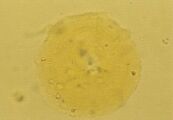

Р

ис. 31. Микрофотография кристалла, напоминающего лейциновый из мочевого осадка 11-летнего самца метиса (не окрашено, увеличение Х 160).